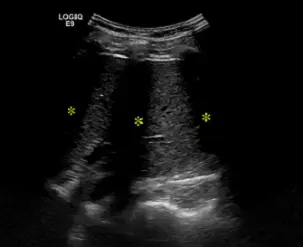

附圖為肝臟超音波掃描影像,圖中三個星號所代表的假影為下列何種原因造成?

- 探頭與掃描部位:影像頂部呈現弧狀 footprint(標示 LOGIQ E9),顯示使用的是腹部超音波常用的曲陣列探頭(Curved array / Convex probe)。畫面中顯示的軟組織為肝臟實質(Liver parenchyma)。

- 假影特徵:在影像中可觀察到三道明顯的、垂直的無回音(Anechoic)黑色帶狀區域,從近端(表淺處)一直延伸至影像最深處。這三道陰影帶邊界相對銳利,且呈現等距分佈。三個黃色星號(*)正是標示在此黑色陰影帶中。

- 物理成因對應:這三道黑色帶狀區域是典型的「乾淨陰影」(Clean shadowing)。在進行肝臟超音波時,探頭常需經過肋間(Intercostal approach)。這三道等距的陰影完美對應了人體肋骨的解剖排列位置。當超音波射束撞擊到肋骨皮質骨時,發生了極高的反射與吸收,使得聲波無法穿透,進而在其後